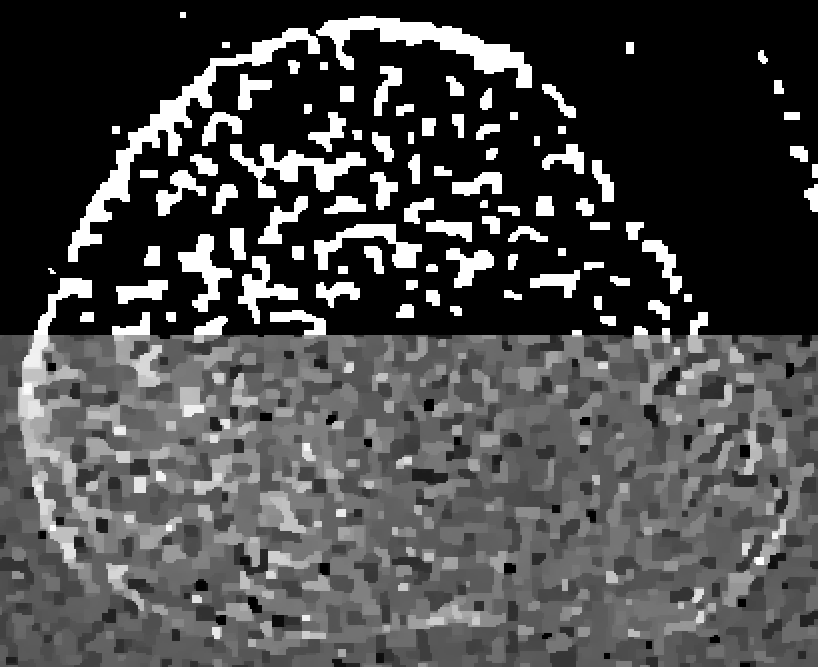

Refer to captionID blurfullRefer to captionshort-1Refer to captionshort-2Refer to captionSI blurRefer to captionRefer to captionRefer to captionSV blurRefer to captionRefer to caption0.0000.0150.0300.0450.060

Figure 4: Reconstructions of the medial bone with the highest mutual overlap over all thresholds and β𝛽\beta’s. The top half of each reconstruction is thresholded.

Figure 4 shows the medial-bone reconstructions (bottom of each image) and segmentations (top of each image) corresponding to the best possible mutual overlap (optimal threshold and β𝛽\beta values) with each scan type and blur model combination. All SV reconstructions depict more trabecular structure than the shift-invariant (SI) or ID models. The difference in image quality among ID reconstructions is readily apparent in these images, with the short-1 scan resulting in the most trabecular detail. Finally, the SI images depict more detail than the ID model but less detail than the SV reconstructions. However, the SI model results in a ringing artifact, particularly evident on the lower left aspect of the medial bone in the full scan reconstruction. This is likely due to blur/model mismatch (the SI model is accurate at the center of the detector but less accurate at the edges).